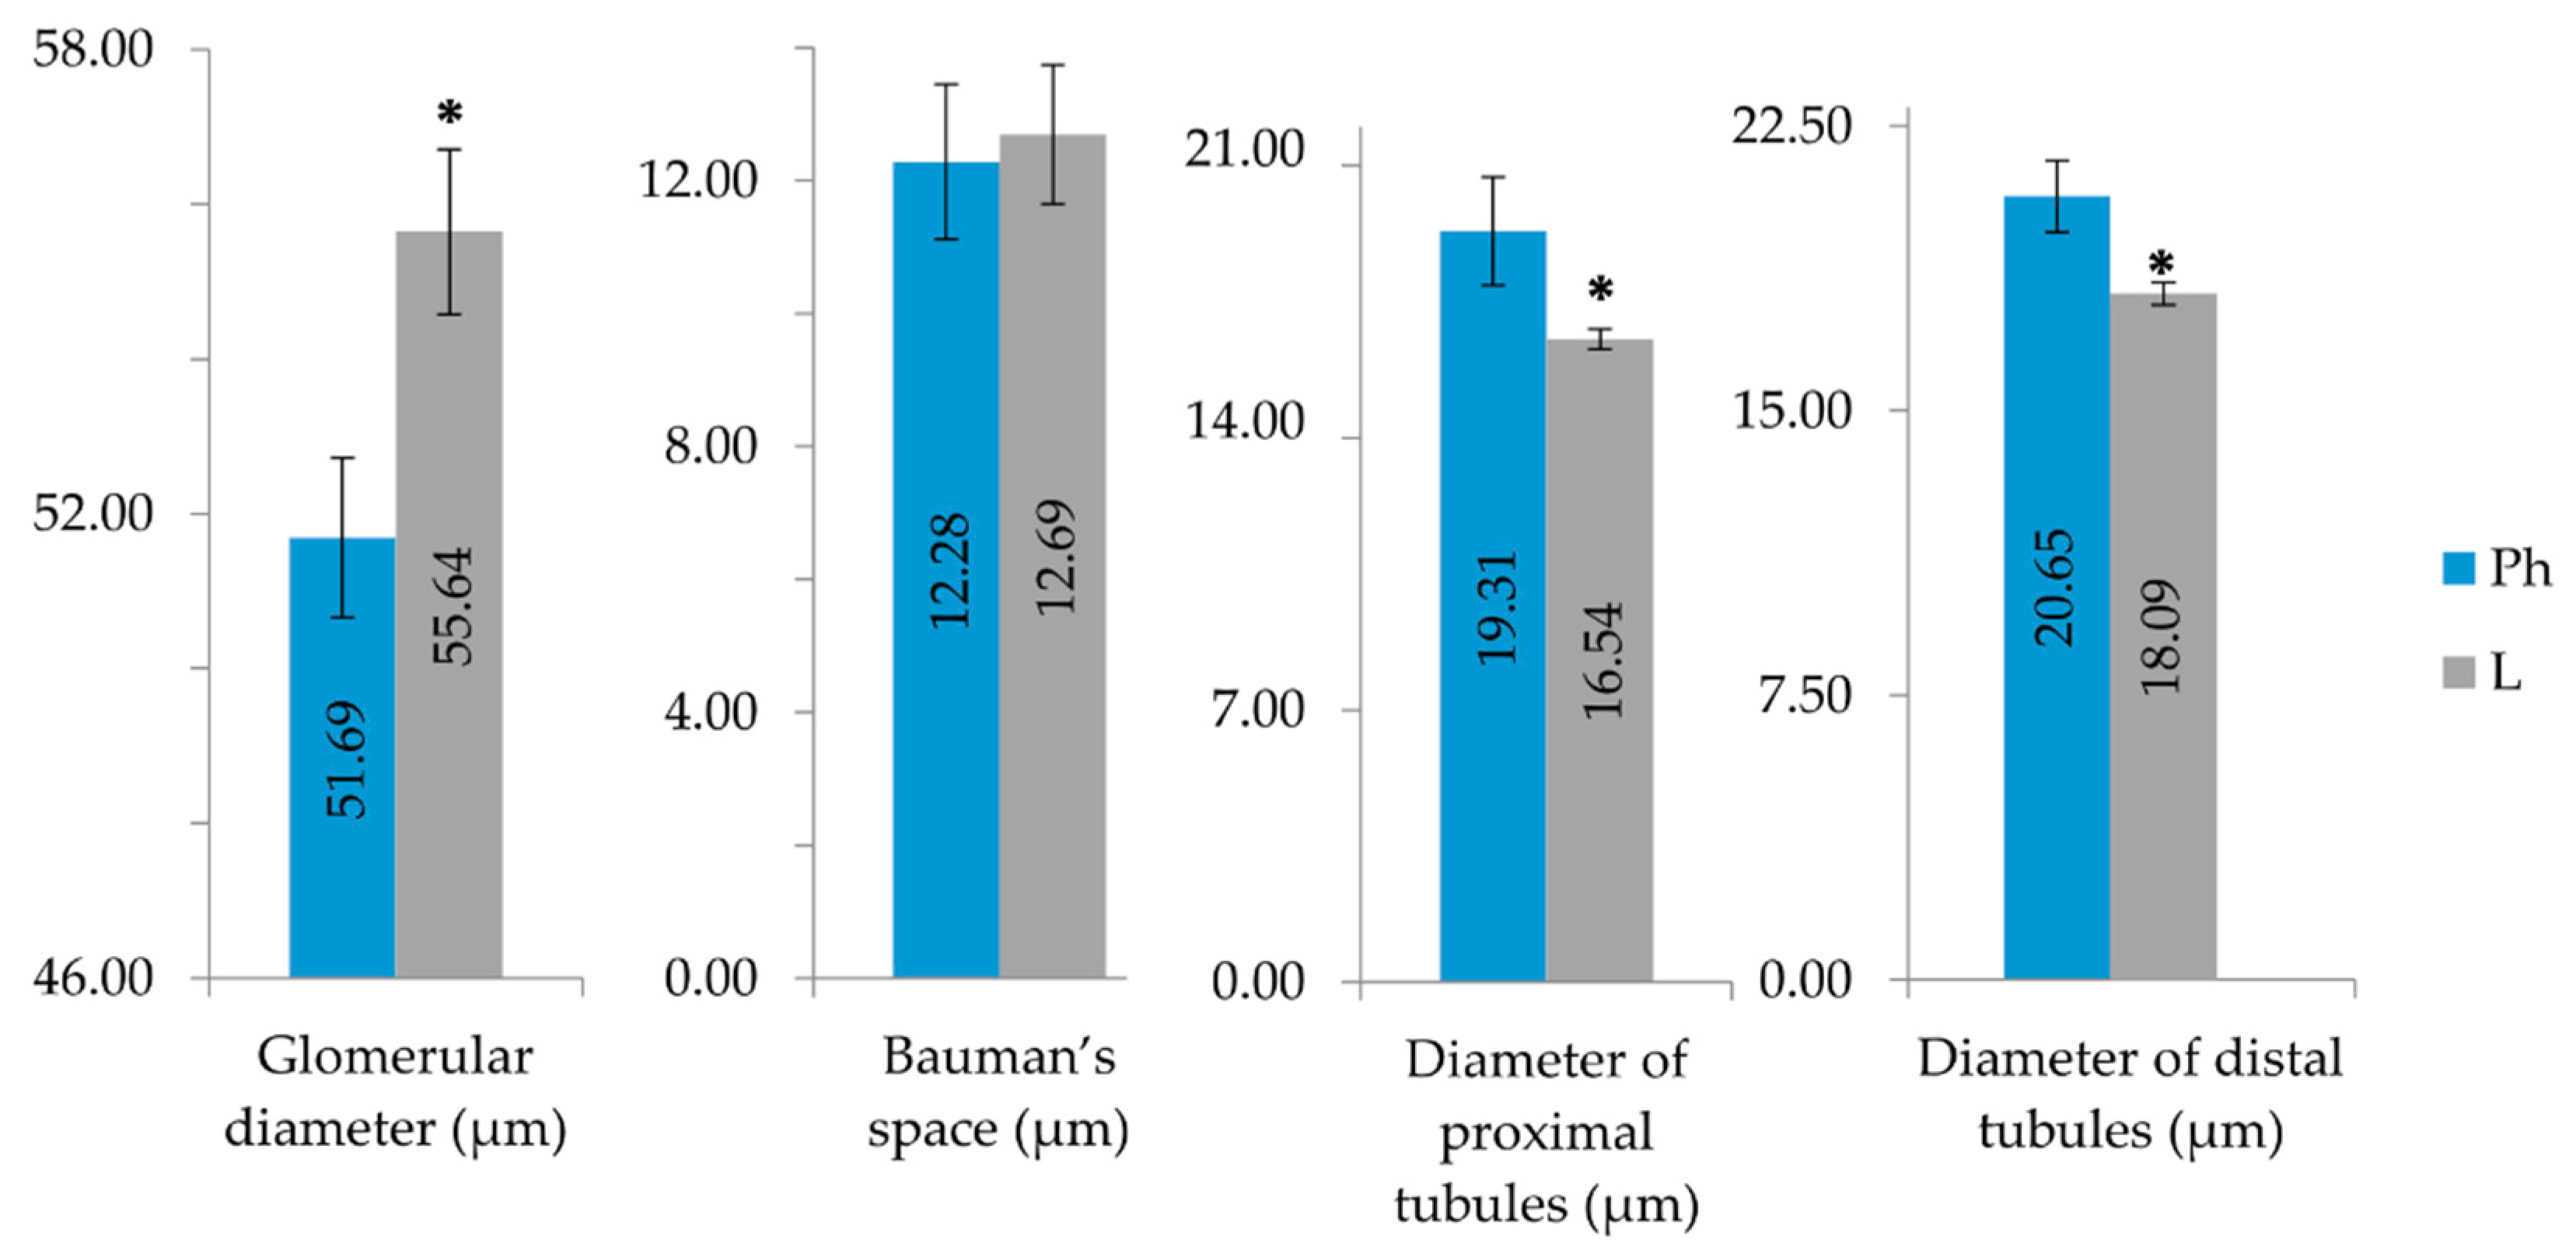

2.3. Purified LysM Lectin Impact to Kidney Morphology

4.5.3. Histological Analysis of Kidney Samples